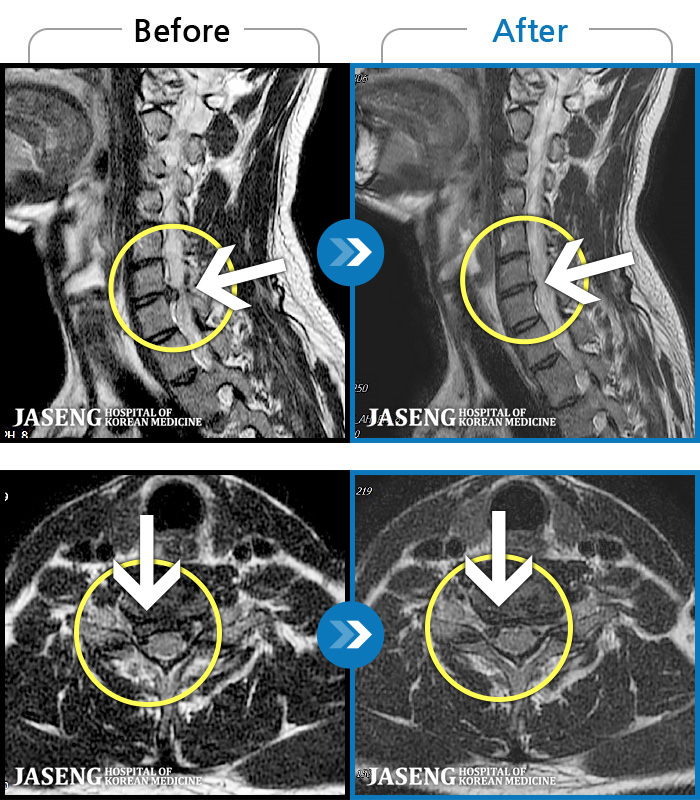

[] 03.04.01~09.11.01